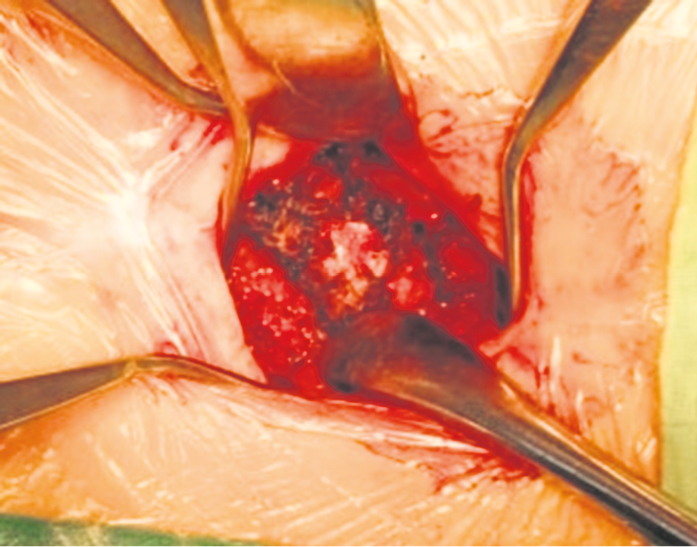

Второе клиническое наблюдение. Пациентка Б., 39 лет, находилась на лечении в клинике военной травматологии и ортопедии Военно-медицинской академии им. С.М. Кирова в июне 2019 г. Травму копчика получила 16 месяцев назад, катаясь на «ватрушке». Получала длительное консервативное лечение по поводу кокцигодинии (физиотерапия, анальгетики, блокады) с временным эффектом. По данным лучевого исследования выявлен застарелый подвывих копчика кзади и наличие костной «спикулы», спонтанный «костный блок» на уровне крестцово-копчикового сочленения (рис. 4). При ректальном исследовании обнаружена значительная подвижность копчика, сопровождающаяся выраженной болью. В клинике больной выполнена резекция копчика, послеоперационное течение без осложнений (рис. 5–8). Пациентка выписана на 4-е сутки после операции. Индекс ВАШ через 1 месяц после операции составил 2 балла, а при дальнейшем наблюдении — 1 балл. По шкале удовлетворенности операцией — «полностью удовлетворена».

Рис. 5. Вид операционной раны пациентки Б. перед резекцией копчика

Fig. 5. Intraoperative photograph of the patient B. before resection of coccyx